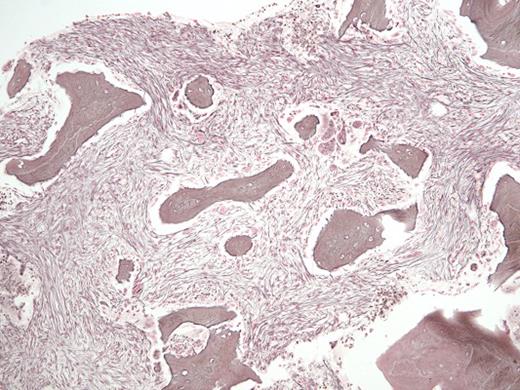

A 29-year-old man with a history of recurrent necrotizing pancreatitis and end-stage renal disease on intermittent hemodialysis was referred for outpatient consultation. He has no history of bruising or bleeding but was recently found to have pancytopenia. A CBC revealed a white blood cell count of 1.6 × 109/L, absolute neutrophil count of 0.4 × 109/L, hemoglobin of 9.1 g/dL, and platelet count of 83 × 109/L. A bone marrow biopsy (Figure 1, hematoxylin and eosin stain; Figure 2, reticulin stain) is shown in the images.

Hematoxylin and Eosin Stain. Hematoxylin and eosin stain in a 29-year-old man with a history of recurrent necrotizing pancreatitis and end-stage renal disease.

The H&E stained bone marrow slide demonstrates increased numbers of immature-appearing osteoblasts seen at sites of osteoid deposition (upper right; normal ~40% of trabecular bone surface area), opposite increased numbers of multinucleate osteoclasts seen at sites of resorptive surfaces (center; normal <2% of trabecular bone surface area). The high dynamic bone turnover rate created by these increased numbers of cells leads to thin and scalloped appearing trabecular bone, with increased amounts of immature woven osteoid seen on trichrome staining (not shown). The reticulin stained bone marrow slide demonstrates areas of diffuse, dense increases in reticulin fibers with extensive intersections and coarse bundles of collagen, consistent with MF-3 grade fibrosis (upper right); interspersed with areas of less dense fiber deposition consistent with MF-2 grade fibrosis (center). The remainder of his laboratory testing was unremarkable, including serum iron and ferritin levels, serum and urine paraprotein studies, inflammatory markers, thyroid hormone levels, and vitamin B12 and folate levels. Subsequent chromosomal analysis revealed a normal 46, XY karyotype, and testing for the JAK2 V617F, BCR-ABL1, MPL W515 L/K, and CALR exon 9 mutations were all negative.